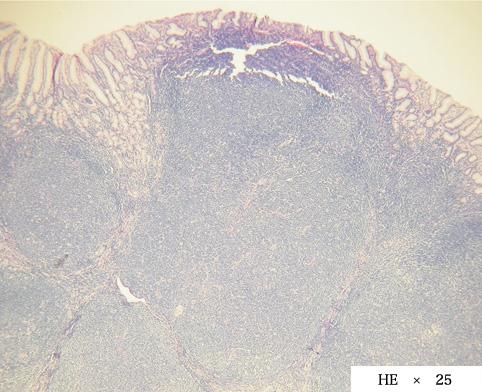

clasificación del pacienteTumor Maligno del Sistema Linfático/Linfoma Maligno

parte(separada por órganos)estómago(región)/cuerpo

método de exámenMicro

clasificación ectoscópica de tumoresTipo 0(tipo superficial)/Tipo IIa(IIa+IIc)

diámetro mayor del tumor15 - 19

grado de penetraciónsm